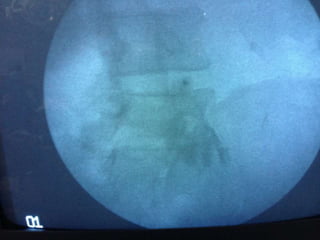

 Material and methods:

 Percutaneous ablating techniques of intervertebral disc are performed

under fluoroscopy guidance with patients in prone position for lumbar

discectomy.

 Pre-procedural antibiotic (Amoxiclav 1.2gm) was given 45 minutes prior

to the procedure.

 Under all aseptic precautions, standard ASA monitored attached , iv line

secured with 20 gauge iv cannula and iv fluid started @ 100ml/hr

 Conscious sedation was attained with intravenous midazolam 1mg and

IV fentanyl 1mcg/ Kg and repeated if required.

 Intervertebral disc of interest was squared in antero-positerior

projection. Scotty Dog projection was attained in oblique view.

 Percutaneous Needle was placed under local anesthesia under C-arm

guidance with Utmost care to avoid nerve roots contact and whenever patient

complain of pain radiating to legs the direction of needle was changed.

 Needle advancement was performed under fluoroscopic control with AP

and Lateral views.

 Annulus fibrosus puncture can be both felt as well as seen under

fluoroscopy.

 Working distance of disc was determined and needle guard was placed

accordingly.

 Stylet was removed and Stryker decompressor was placed in a needle

and properly locked.

 The decompressor was switched on and needle and decompressor

were moved as a single unit over a distance of one centimeter or as

directed by C-arm picture and about 1-1.5ml of gelatinous nucleus

pulposus was removed.

 After completion of procedure 1ml of injection Acuclav was given in

the disc space.

 Assembly was removed and aseptic dressing was applied.

 The patient was asked to move his lower limb to check any injury to

nerves by comparing with other side.

 Patient kept in recovery for 3 hrs and sent home if fit with clear

instructions to accompanying person.

.  Material andmethods:  Percutaneous ablating techniques of intervertebral disc are performed under fluoroscopy guidance with patients in prone position for lumbar discectomy.  Pre-procedural antibiotic (Amoxiclav 1.2gm) was given 45 minutes prior to the procedure.  Under all aseptic precautions, standard ASA monitored attached , iv line secured with 20 gauge iv cannula and iv fluid started @ 100ml/hr  Conscious sedation was attained with intravenous midazolam 1mg and IV fentanyl 1mcg/ Kg and repeated if required.  Intervertebral disc of interest was squared in antero-positerior projection. Scotty Dog projection was attained in oblique view.  Percutaneous Needle was placed under local anesthesia under C-arm guidance with Utmost care to avoid nerve roots contact and whenever patient complain of pain radiating to legs the direction of needle was changed.  Needle advancement was performed under fluoroscopic control with AP and Lateral views.

 Annulus fibrosuspuncture can be both felt as well as seen under fluoroscopy.  Working distance of disc was determined and needle guard was placed accordingly.  Stylet was removed and Stryker decompressor was placed in a needle and properly locked.  The decompressor was switched on and needle and decompressor were moved as a single unit over a distance of one centimeter or as directed by C-arm picture and about 1-1.5ml of gelatinous nucleus pulposus was removed.  After completion of procedure 1ml of injection Acuclav was given in the disc space.  Assembly was removed and aseptic dressing was applied.  The patient was asked to move his lower limb to check any injury to nerves by comparing with other side.  Patient kept in recovery for 3 hrs and sent home if fit with clear instructions to accompanying person.